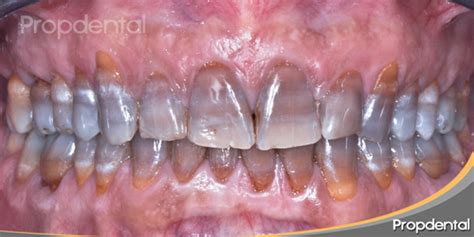

Según estudios relacionados, la tinción se origina durante el proceso de formación de la dentina. La tetraciclina tiende a unirse con el calcio, por lo que oscurece la composición que conforma los dientes, huesos y articulaciones. En consecuencia, no se trata de una mancha superficial, sino que es parte del material que conforma la propia pieza dental al formarse. Dicho de otra manera, el diente es grisáceo desde su interior.

En función del grado de coloración se establecen cuatro categorías. Desde una leve variación cromática, que por lo general tiende a un color gris, hasta el nivel más extremo y poco común, que produce alteraciones en la textura dental y rallas horizontales que varían en cromatismo. Estudios recientes, llevados a cabo en gente adulta, han demostrado que altas dosis de esta composición pueden producir también este efecto en adultos, aunque se trata de un fenómeno más extraño.